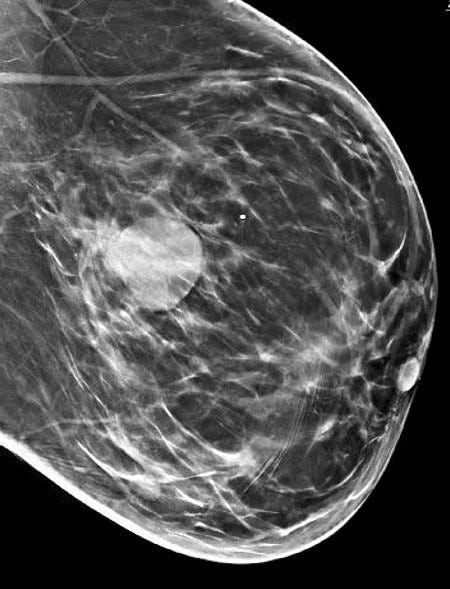

Medullary carcinoma of the breast is a rare subtype (3 - 5%) of invasive breast cancer with pushing borders, syncytial growth, high grade nuclei and a prominent lymphoid infiltrate. According to the World Health Organization, the preferred terminology is invasive breast carcinoma of no special type with medullary pattern.

Grossly, the tumors are usually 2 - 5 cm, well circumscribed, soft to firm, lobulated masses. Although they appear sharply demarcated from surrounding tissue, they lack a true capsule and may exhibit pushing, expansile borders without widespread stromal invasion.

Microscopically, medullary carcinoma is composed of large, pleomorphic, high grade tumor cells arranged in broad syncytial sheets occupying at least 75% of the tumor area. The tumor cells have vesicular nuclei (i.e., large, pale staining with a central clearing) with prominent nucleoli and abundant eosinophilic cytoplasm. A prominent and dense lymphoplasmacytic infiltrate surrounds and often infiltrates the tumor, suggesting a vigorous host immune response. Mitotic figures are numerous and areas of necrosis may be present.

Medullary carcinoma - radiologic and microscopic images